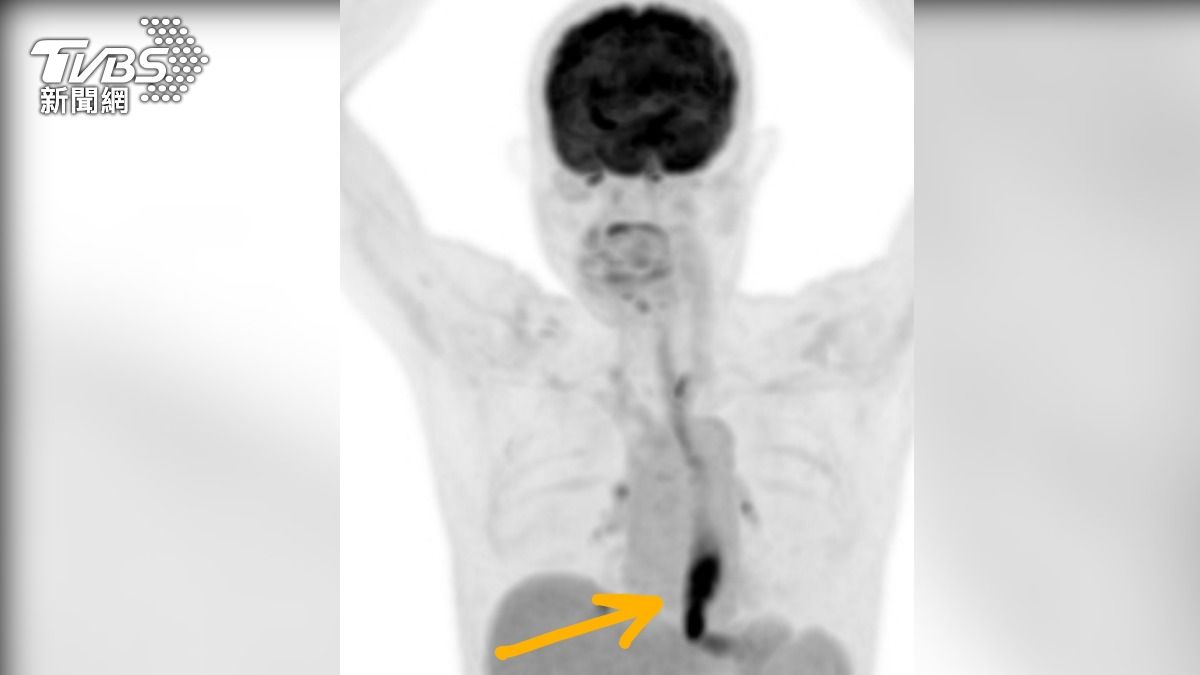

台中市一名58歲的男子,從成年後就開始抽菸、喝酒,並持續40年,但日前他突然出現吃飯會痛、吞不下去的症狀,於是前往澄清醫院中港院區就診,一經安排內視鏡就在食道看見明顯腫瘤,隨後男子轉至胸腔外科尋求醫師杜承哲協助,經切片化驗有五顆淋巴結轉移,確診食道癌第三期,對此,杜承哲也表示,食道具彈性,往往有特殊症狀出現時,腫瘤都已經長得非常大,若再拖下去,食道癌第四期的五年存活率通常低於10%,且復發率又高。